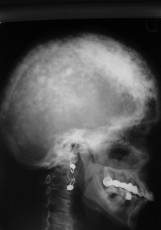

MIELOMUL MULTIPLU

Aspectul radiologic

La nivelul craniului se evidentiaza zone de osteoliza rodunde de dimensiuni variabile în jur de 10mm cu contur net aratând ca niste gauri facute cu burghiul.